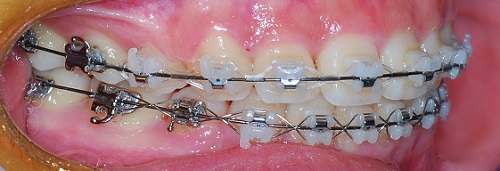

치과쌤이 치아를 쭉보시고 와이어를 얇은것으로 바꿔주셧어요.

드뎌드뎌 치아교정 마무리 작업에 슬슬 들어가는군용!

발치 공간은 다 닫혓어요. ^__________^

(측면사진)

측면에서도 치아 사이에 구멍은 보이지 않아요!